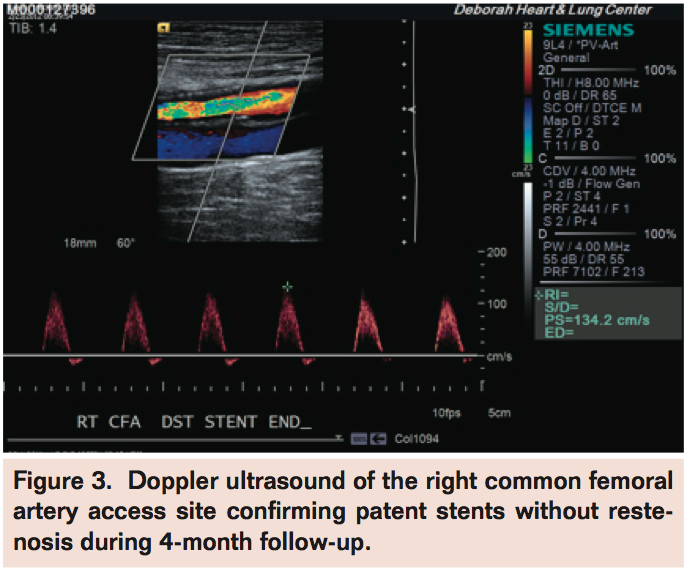

Selective angiogram of the right CFA showed patent stents (Figure 2) with mild-to-moderate disease in the distal SFA and 2-vessel runoff into the right foot. A Mynx with Grip Technology (AccessClosure, Inc) vascular closure device (VCD) was deployed in the right CFA with adequate hemostasis and the patient discharged home the following day without complications.